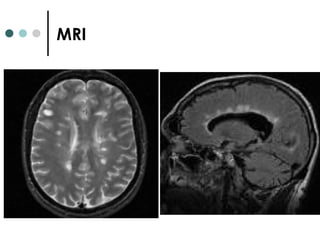

Progressive Multifocal

Leukoencephalopathy (JC virus)

• #37 In the upper row on the left, CT shows lesions fewer lesions and reveals a smaller affected area than MRI. In the middle column a large, hypointense lesion can be seen in the region of the right occipital lobe (angular gyrus and intraparietal sulcus) in a T1 weighted image. On the right, a T2 weighted image reveals the typical, multifocal affection of PML with additional lesions in the white matter of the left frontal lobe and the white matter of the tempoaral and occipital lobe. Note sparing of grey matter. In the lower row, CT shows contrast enhancement in the right cerebral peduncles as does MRI with Gadolineum in the middle column. On the right, T2-weighted imaging, an additional hyperintense lesion can be seen in the white matter in the inferior posterior temporal gyrus on the right.